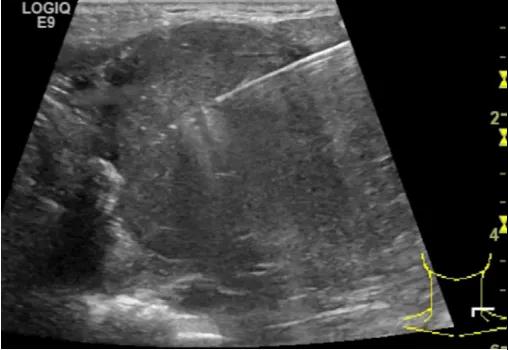

随后,徐栋教授进一步分享了五个临床实战病例,带来了更直观的热消融治疗经验。第一个病例是62岁肺癌患者,术后1年余发现双侧锁骨上淋巴结复发,侵犯神经,存在静脉回流、淋巴回流障碍,肿胀、疼痛非常明显。影像显示患者淋巴结边界不清、形态不规则,存在浸润,血流强化增强。由于患者在系统治疗后进展,且主要目的缓解症状、减瘤。局麻下行热消融术,从后向前逐层消融,热消融之后超声造影即刻评估显示完全充盈缺损,完全覆盖病灶。

(病例1图例)